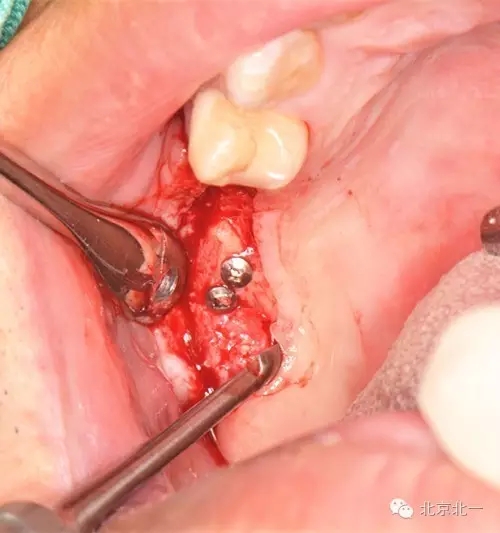

圖六:修整骨塊

圖七:骨塊堅(jiān)強(qiáng)內(nèi)固定

圖八:骨替代品協(xié)同使用。